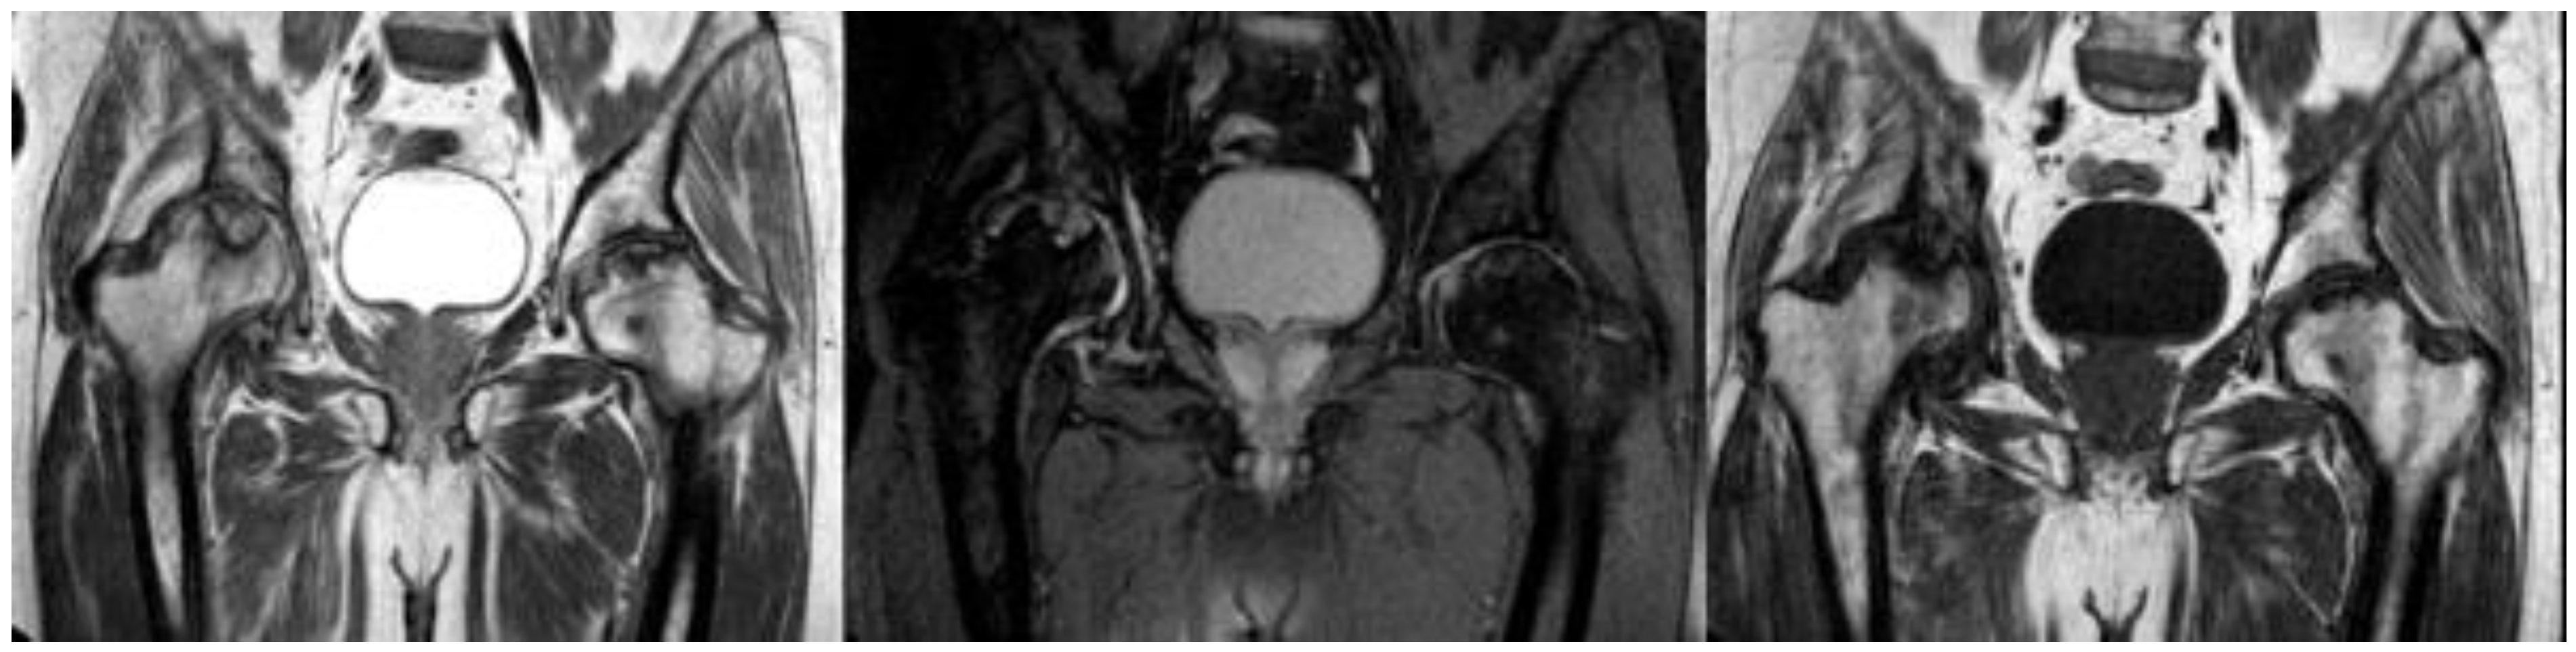

| 14. Kashkosh et al. (2022) [15] | Case report | 1 M | 40 | Second dose of the Pfizer COVID-19 vaccine | AVN of the humeral head | 2 | Analgesics Activity modification IA hydrodilatation inj | Improved ROM Severe shoulder pain Surgical intervention |